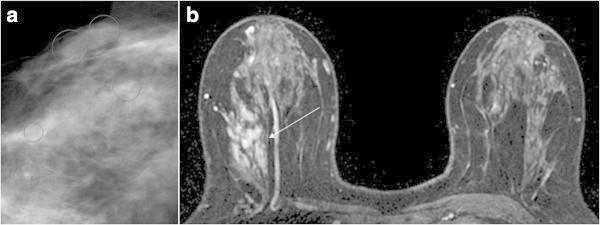

The purpose of this study was to assess indications for stereotactic vacuum-assisted breast biopsy (SVAB) evaluated by breast 3 T-magnetic resonance (3 T-MR) imaging in patients showing suspicious microcalcifications on mammography and negative ultrasound (US) findings.

Fifty-five patients with 55 breast lesions showing suspicious microcalcifications on mammography and negative US findings underwent preoperative 3 T-MR examination including dynamic MR imaging. All patients underwent SVAB within 1 month of MR imaging. The pathological diagnosis of each breast lesion was made by examining tissues obtained by SVAB or radical/partial mastectomy. 3 T-MR imaging findings were evaluated by using the American College of Radiology Breast Imaging Reporting and Data System Atlas (BI-RADS-MRI) and then were correlated with the histopathological findings. When BI-RADS 4 and 5 MR imaging lesions were assumed to be malignant, the usefulness of 3 T-MR imaging was evaluated for diagnosis of impalpable breast lesions by SVAB among lesions with microcalcification detected by mammography and negative US findings.

There were 21 malignant lesions, including 5 invasive ductal carcinomas, 16 lesions of ductal carcinoma in situ (DCIS). The sensitivity, specificity, positive predictive value, negative predictive value, and accuracy of 3 T-MR imaging for deciding the indications for SVAB was 90.5%, 97.1%, 95.0%, 94.3%, and 94.5%, respectively. The one-false negative case was a DCIS with small enhancing lesions (0.5 mm). The one false-positive case was ductal adenoma with a linear ductal pattern of enhancement.

3 T-MR imaging may be useful for deciding the indications for SVAB in patients who have breast lesions with microcalcification that are impalpable and are detected by mammography and negative US findings. However, our findings should be considered preliminary and further prospective investigation is required.